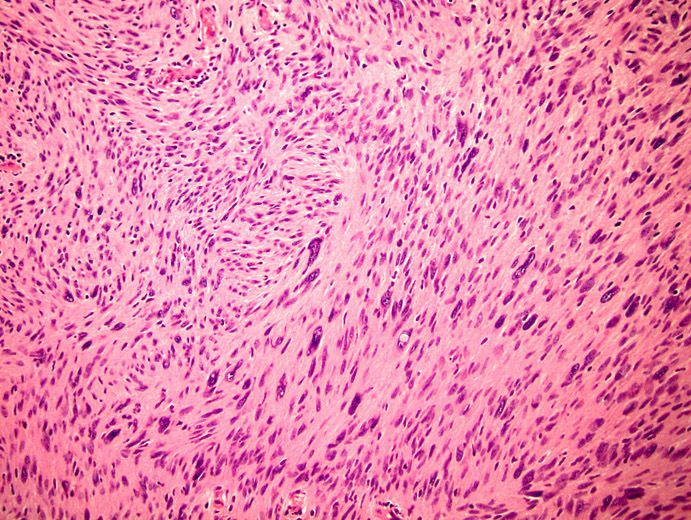

Explain the pictured condition

Traumatic neuroma –> non-neoplastic proliferation associated with previous injury of a peripheral nerve. Try to reconnect/regenerate nerve axons that have been injured, so causes the recruitment of supportive cells to elongate the axons (astrocytes etc.) which form a disorganised lump.